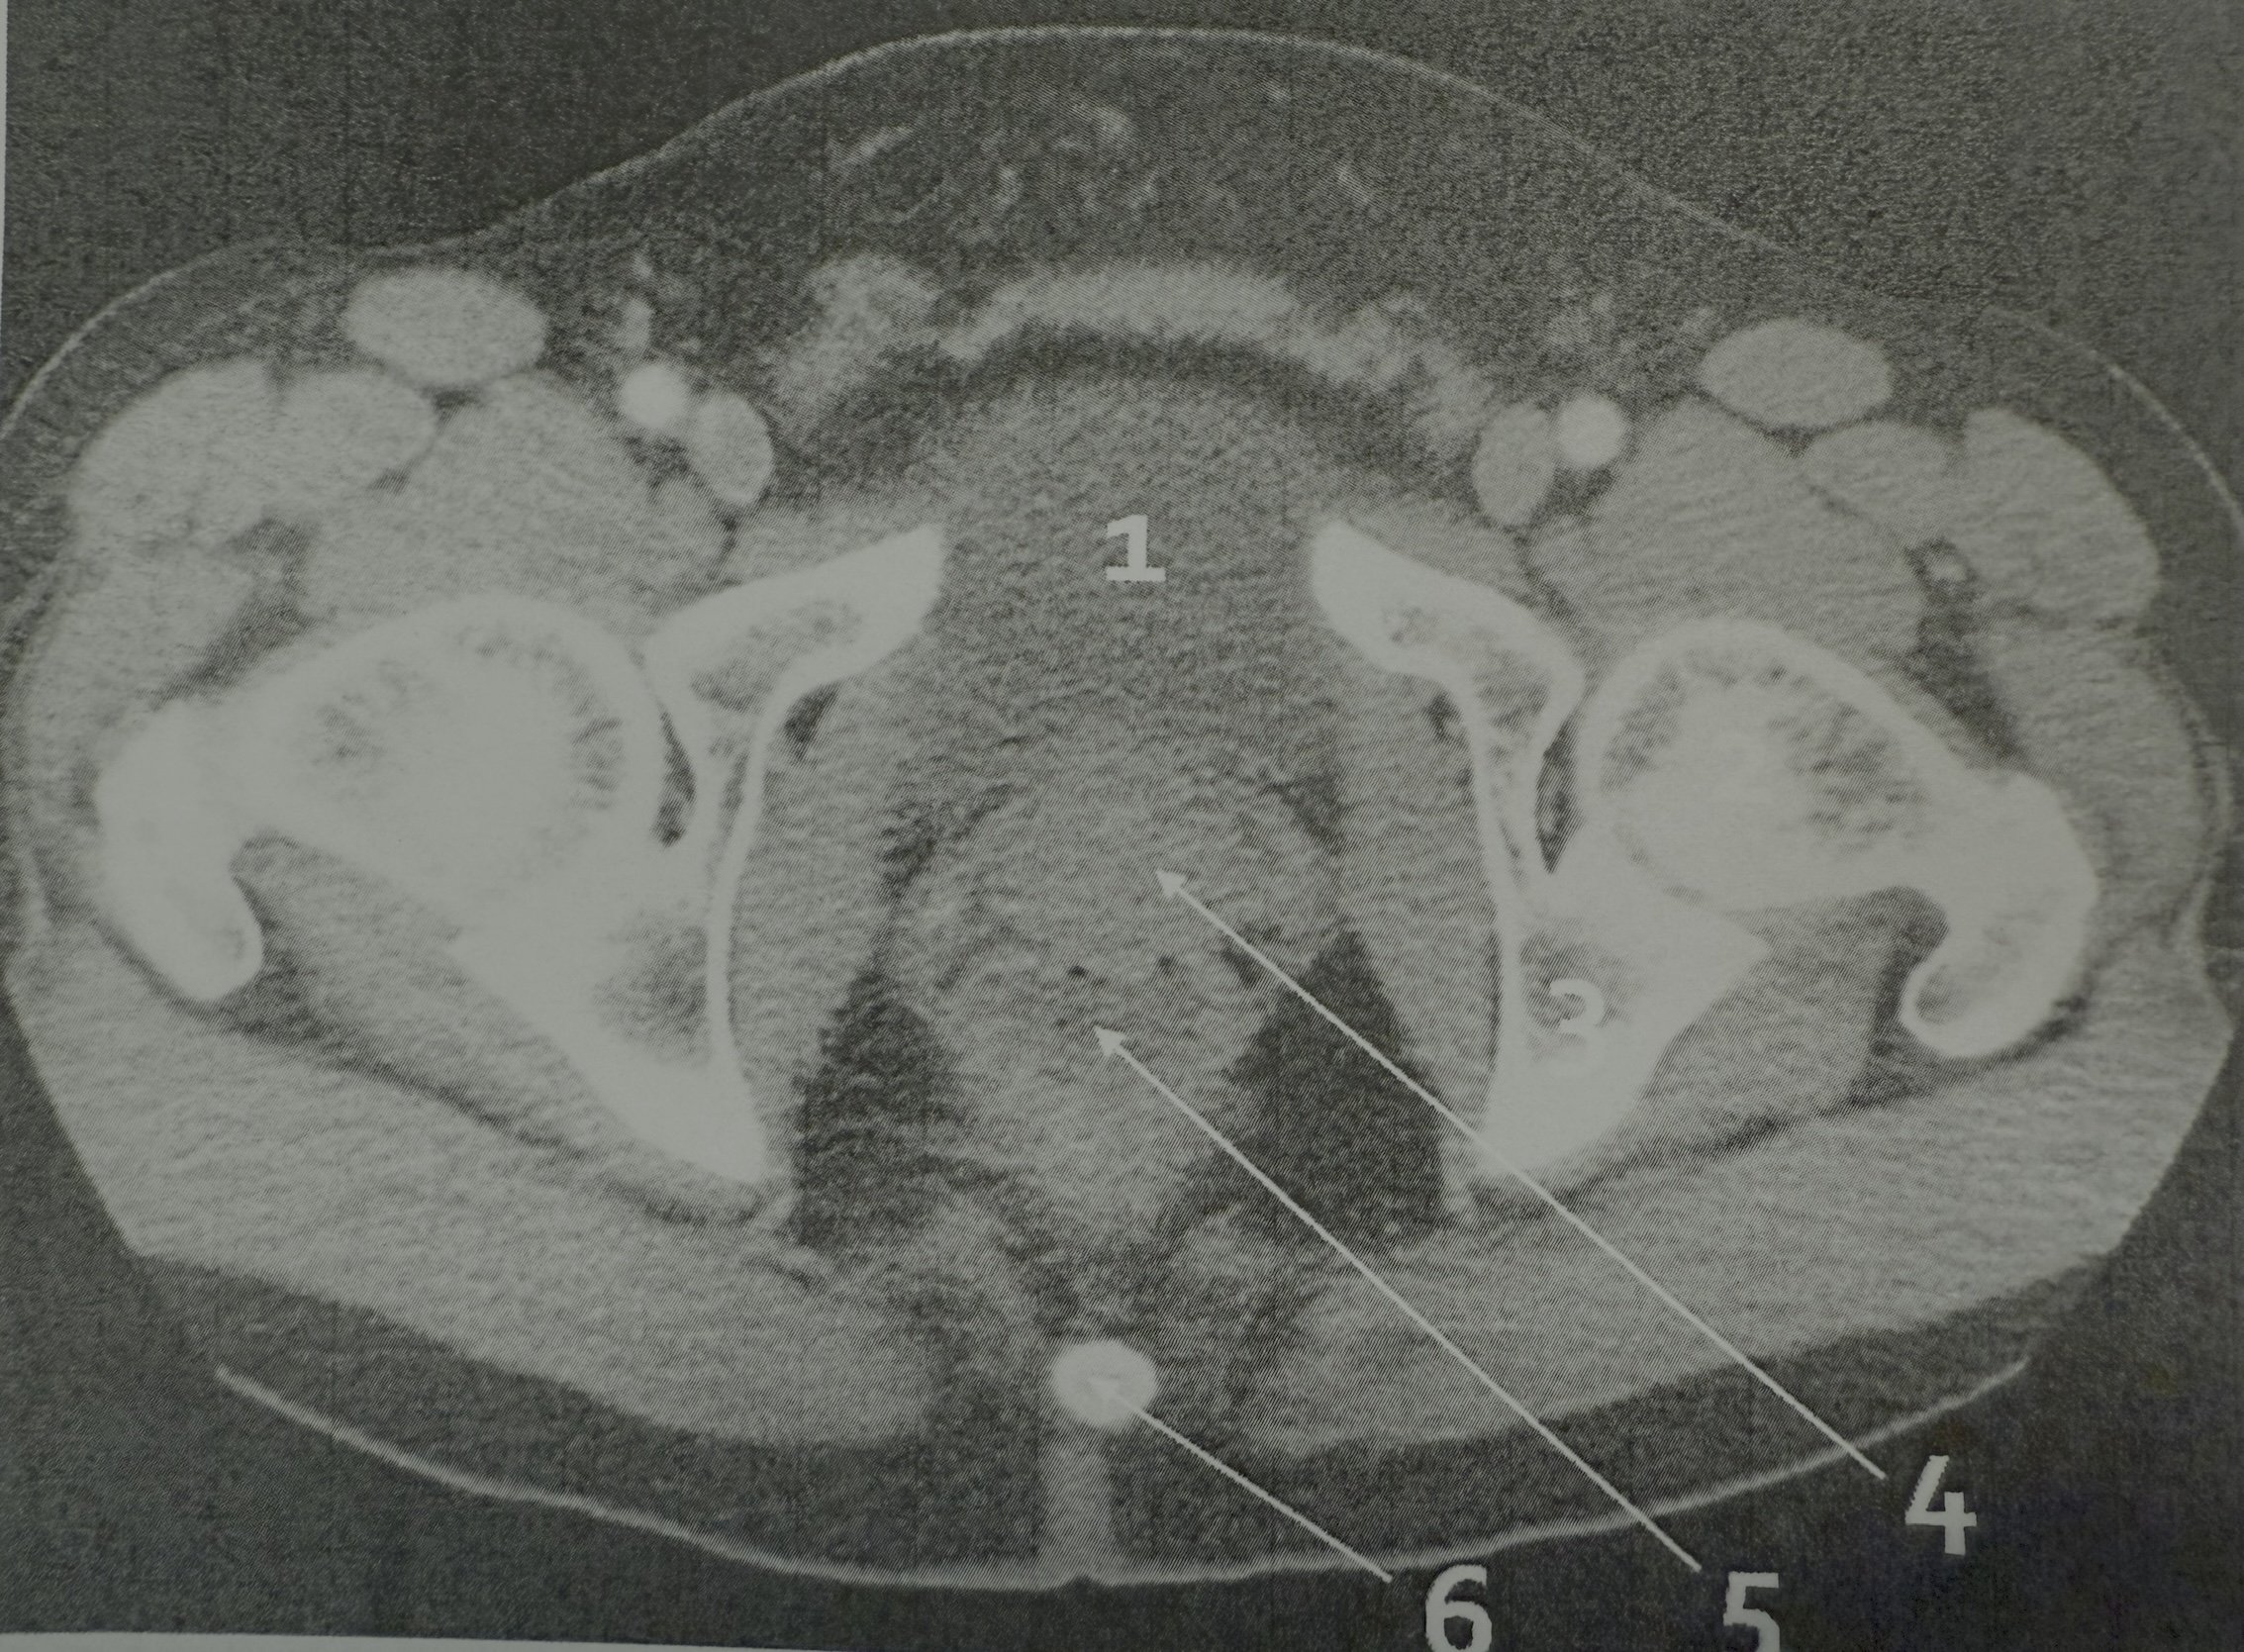

1

bladder

4

sigmoid colon

5

sacrum

2

head of femur

prostate gland

rectum

6

coccyx